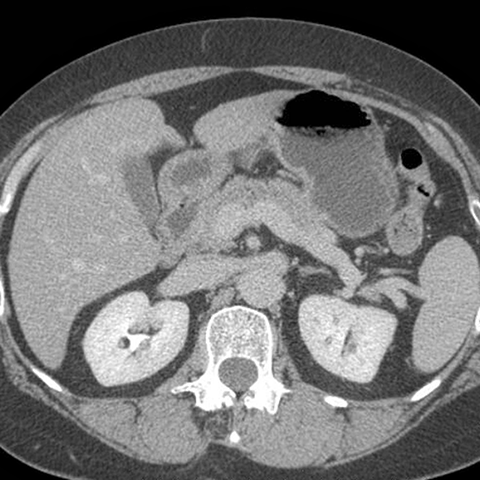

Normal Stomach, axial CT [3 of 4]